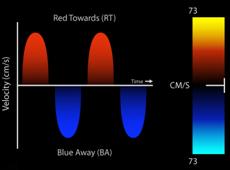

Por convención , el doppler espectral resultante muestra la velocidad en el eje de la Y y el tiempo en el eje X. El flujo que se dirige hacia el transductor, aparece por encima de la línea de base, mientras que el flujo que se aleja, se encuentra por debajo de la línea de base. El Doppler Color, (Figura 9) es una variedad de Pulsado que utiliza una escala de colores, representada, en el flujo laminar, con rojo (flujo que se acerca al transductor) y con azul el que se aleja. Cuando el flujo se hace turbulento, debido a una alteración funcional de la válvula, aparecen los colores amarillo y verde, reflejo de un aumento en la velocidad de la sangre al cruzar una válvula patológica anatómica o funcionalmente(13). (Figura 10)(Figura11)

Rojo positivo y laminar, se acerca a imagen transgástrica (140°), tracto salida transductor. Azul negativo, se aleja el transductor del ventrículo derecho (TSVD).